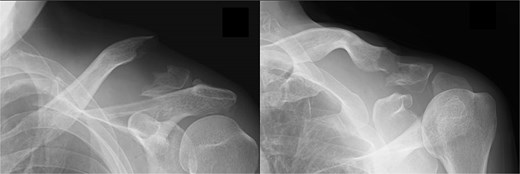

Postoperatively, the left arm of the patient was immobilized in a sling for 3 weeks. The pain gradually subsided, and the patient resumed heavy work without pain at 6 months postoperatively. At 1 year postoperatively, the patient had a constant score of 98. Bone union was confirmed (Fig. 4A–D).

Radiographs (A and B) and CT scans (C and D) captured at 1 year postoperatively show union of the bone.